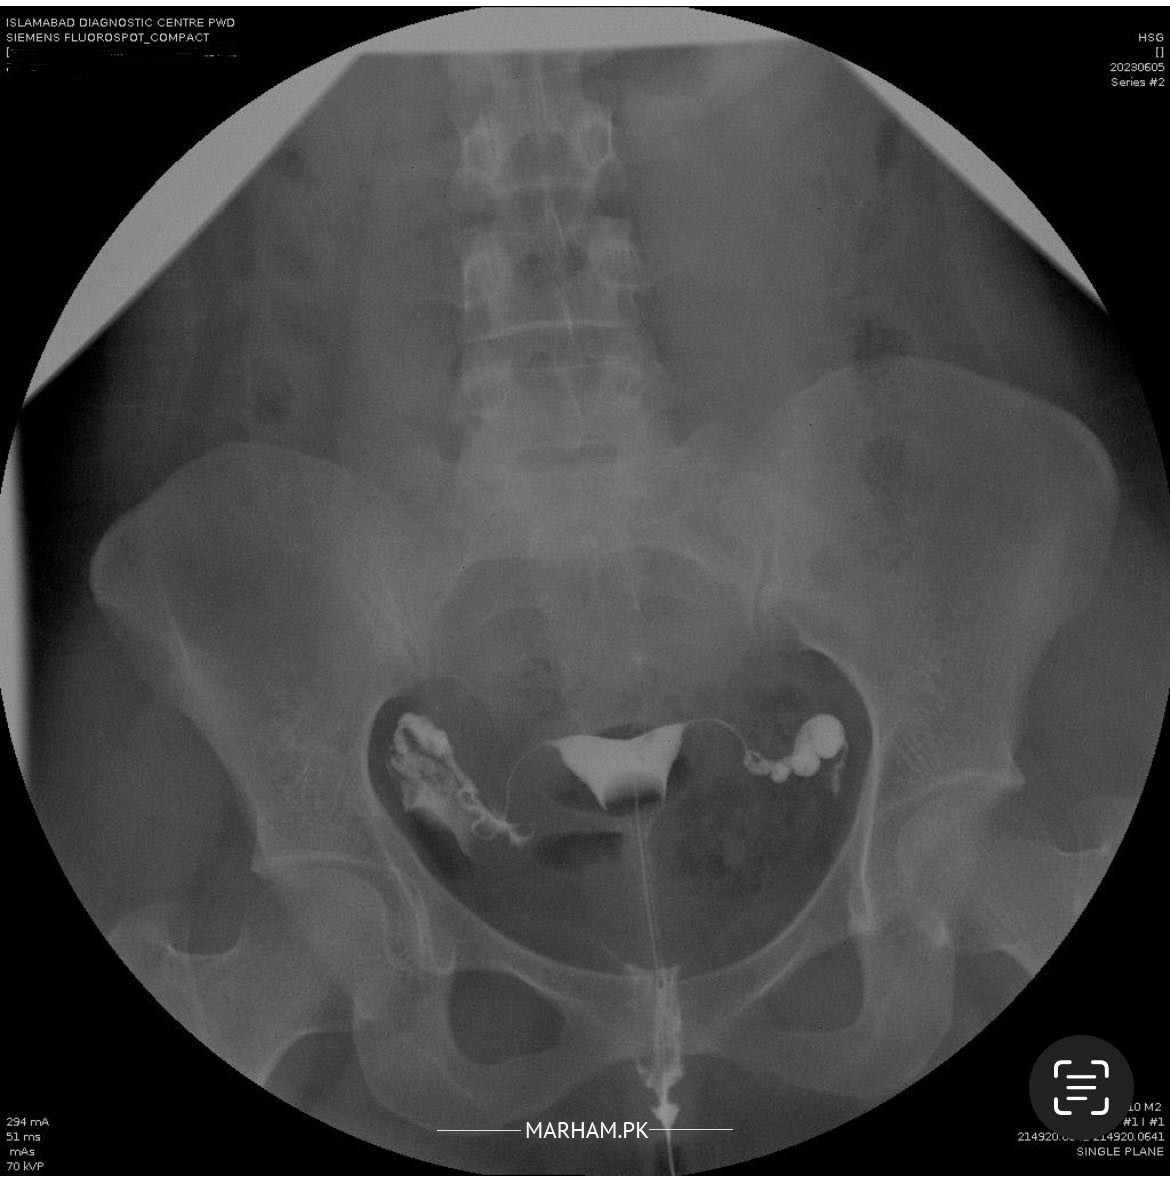

Dear Doctors, We’ve been married for 2.5 years and trying to convince. As doctors have recommended more tests for wife. The recent test did was tube test. Looking for second opinion on reports. Any comments will be appreciated. JazakAllah.

ur tubes r open

the patient tubes are opened we need husband seven analysis report

tubes are open